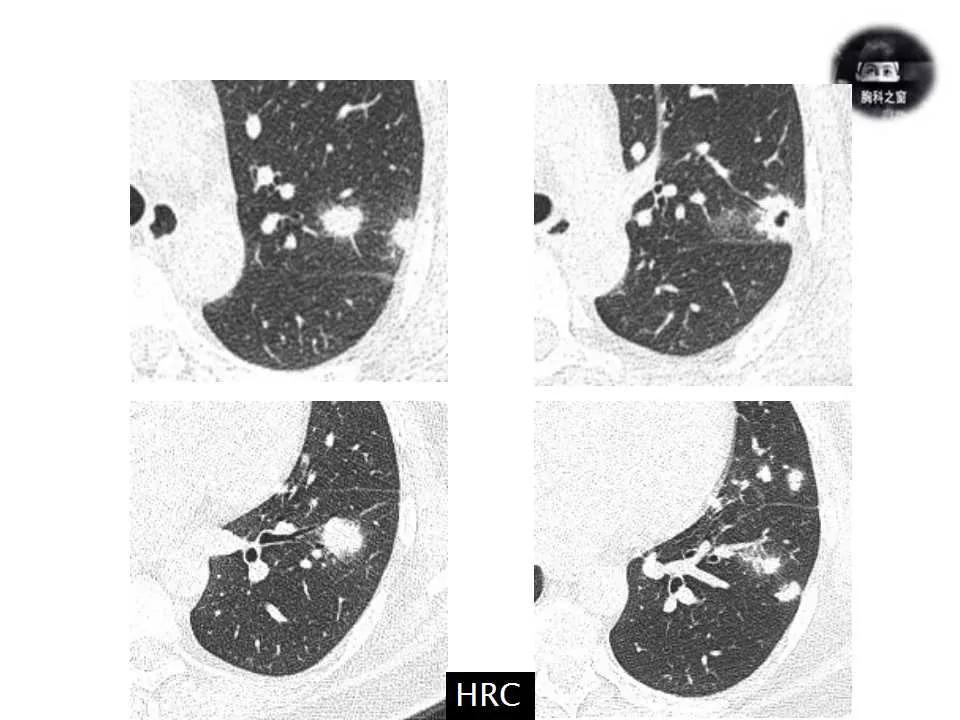

主诉:发现左肺病变1天

现病史:患者1天前体检胸部CT提示左肺病变,之前一段时间进食较少,七月初、七月中旬出现咳嗽、胸痛、无法深呼吸,无咯血,无乏力、盗汗,无明显体重减轻,为接受进一步诊治收入院。(2019.7.30)

影像诊断:真菌性肺炎,隐球菌可能性大。

追问病史,有近距离接触鸽子史。隐球菌抗原(+)。

肺隐球菌病